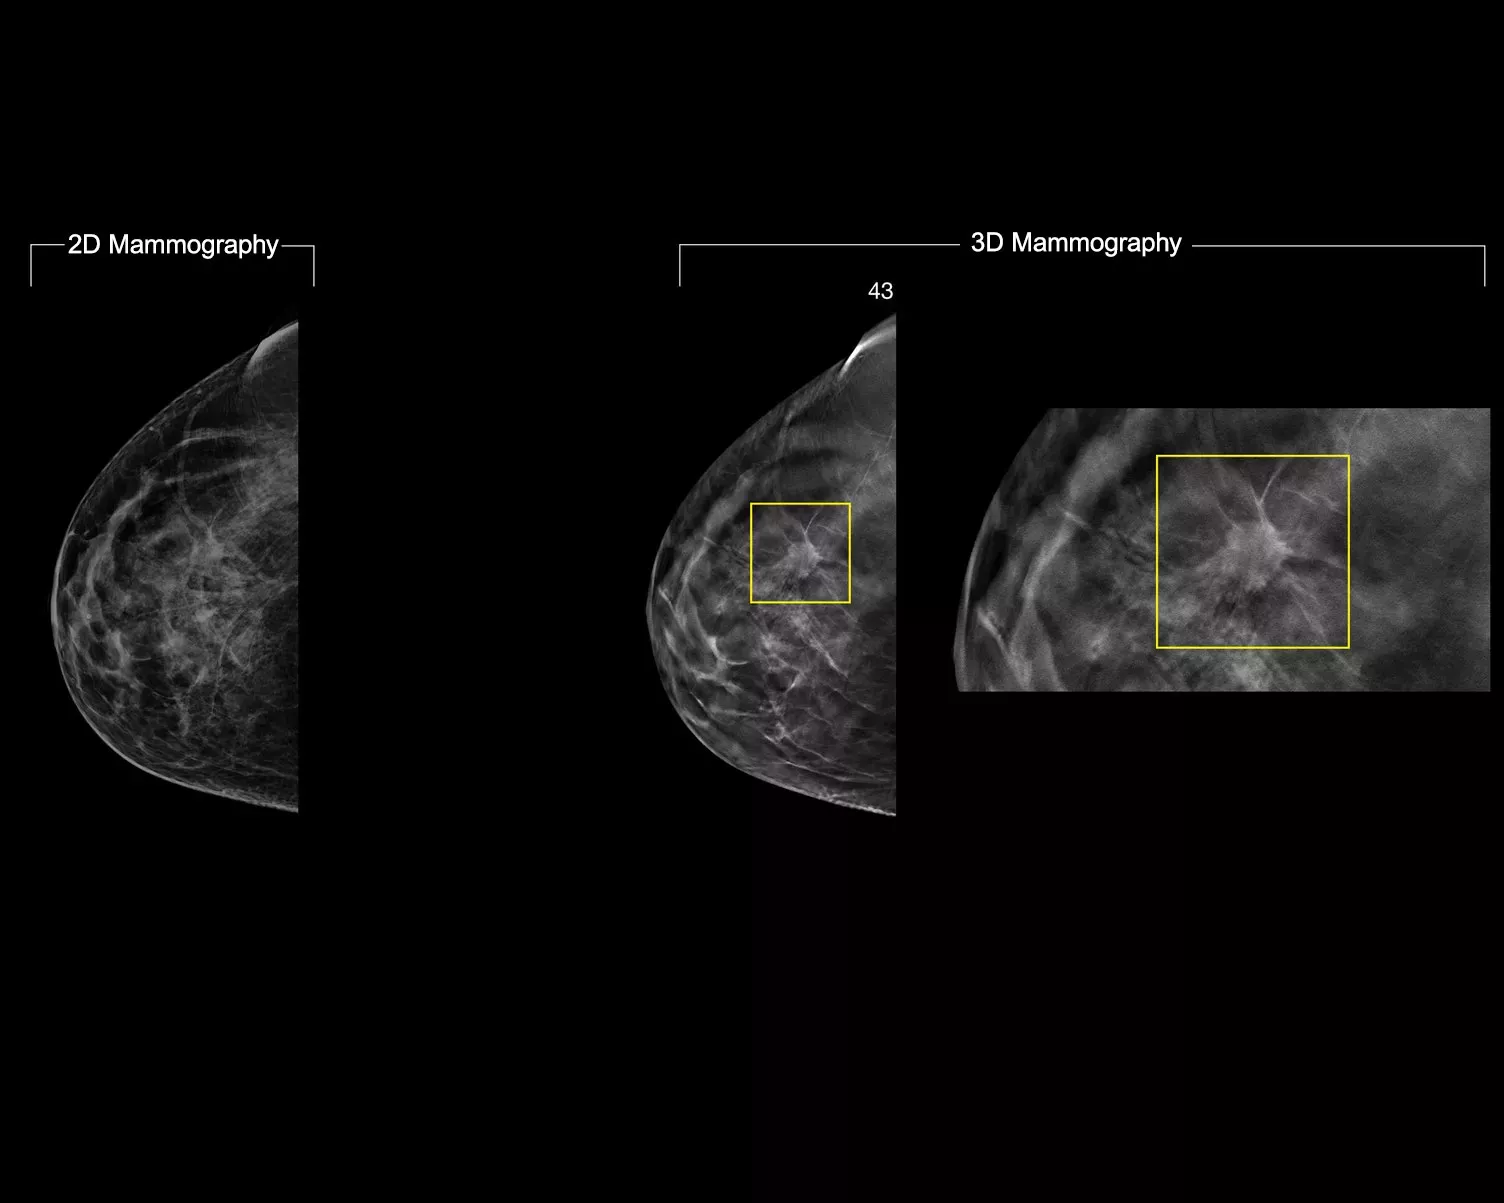

De 3DQuorum technologie reconstrueert met behulp van door Genius AI™ aangedreven analyses op unieke wijze 3D-Mammography™-gegevens met hoge resolutie om SmartSlices van 6 mm te produceren. Dit verkort de beoordelingstijd door het aantal te beoordelen beelden te verminderen, zonder compromissen op het gebied van beeldkwaliteit, gevoeligheid of nauwkeurigheid.2,3 Met onze nieuwste innovatie kunt u de beoordelingstijd met een uur per dag verkorten.2,3*

Genius AI-analyse identificeert aandachtsgebieden (ROI's) en behoudt belangrijke kenmerken tijdens het maken van SmartSlices.2 De 6 mm met 3 mm overlap van SmartSlices voorkomt gegevensverlies en zorgt voor continuïteit bij het scrollen.4-6

Bij het beoordelen van Smart Slices in plaats van slices van 1 mm wordt het aantal te beoordelen 3D™-afbeeldingen met tweederde verminderd.4-6 Dit bespaart gemiddeld 1 uur per dag aan tijd voor beeldinterpretatie.3